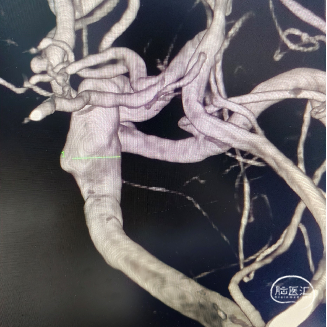

左侧颈内动脉眼动脉段动脉瘤:动脉瘤约为6.21*5.11mm(H*W),瘤颈宽约为4.72mm。

载瘤动脉近端锚定点直径:4.72mm

载瘤动脉远端锚定点直径:3.54mm

本次应治疗的动脉瘤为左侧颈内动脉眼动脉段动脉瘤。动脉瘤为囊状动脉瘤,结合动脉瘤形态学评估推断其破裂风险较低,可选择单纯应用血流导向密网支架进行治疗而无需弹簧圈栓塞,在降低手术难度的同时还可降低动脉瘤继续生长破裂和复发的风险。